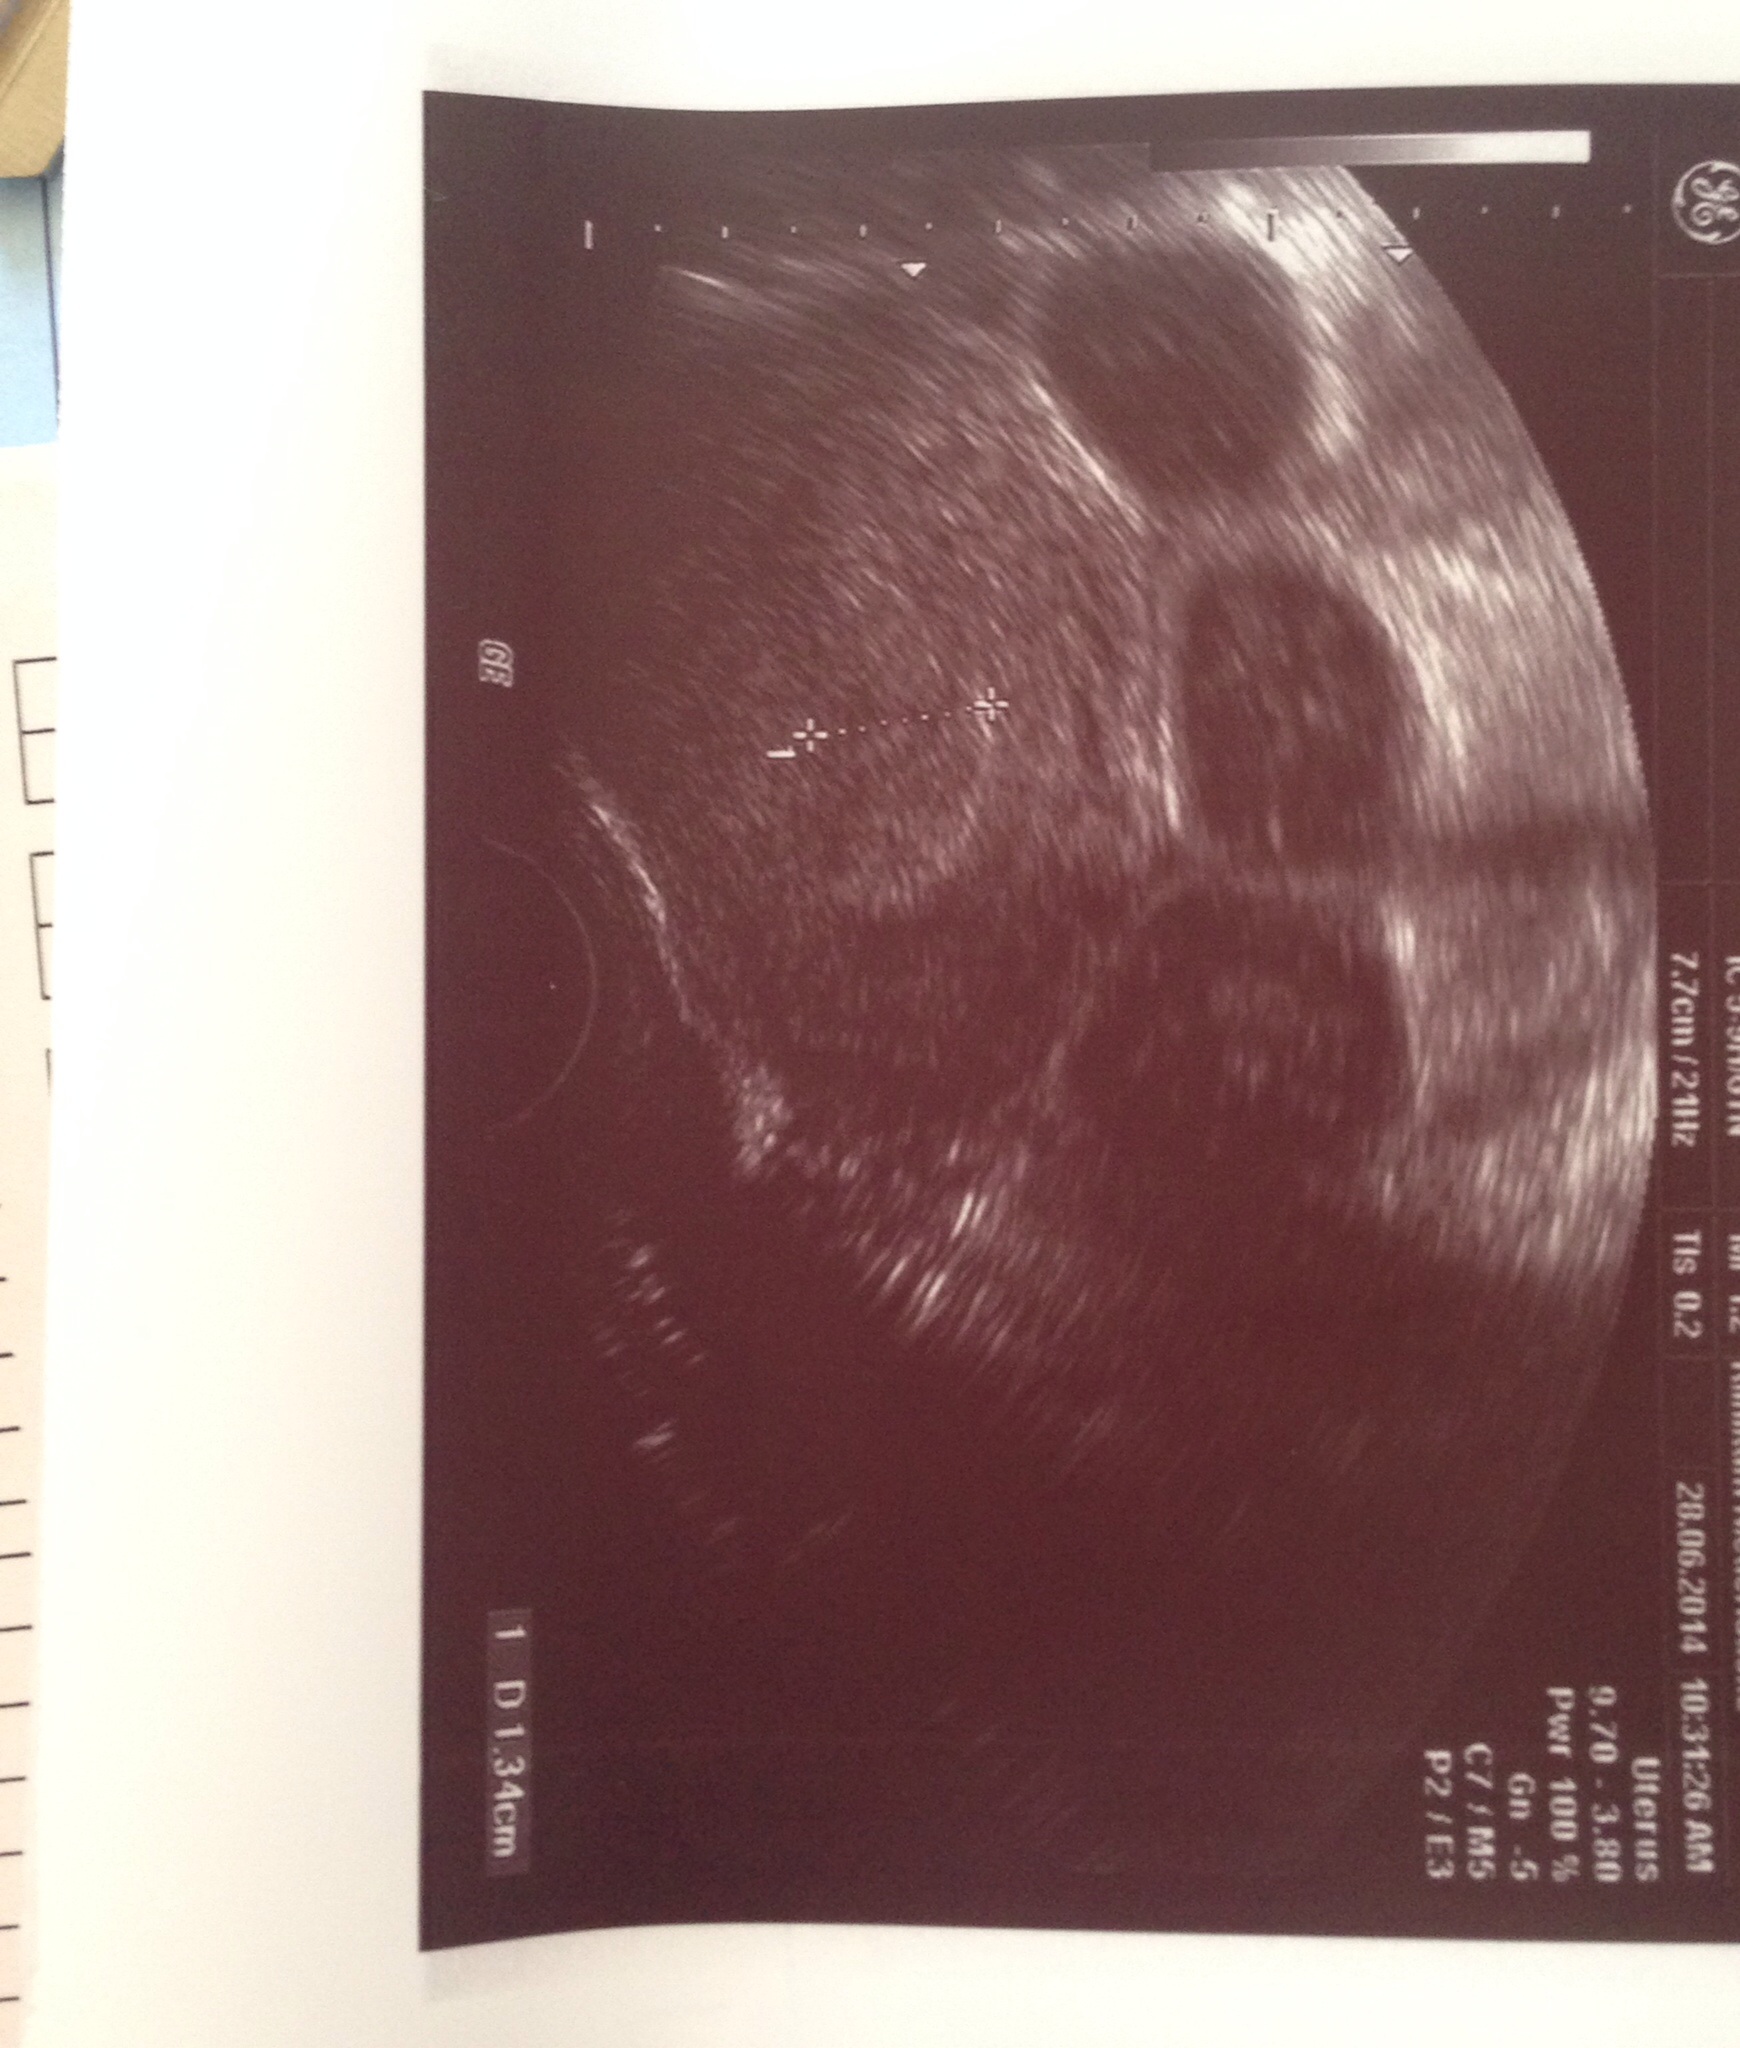

5 ssw ultraschall nichts zu sehen und blutung SSW, da unter einem Ultraschall in der 5 SSW außer einer bohnengroßen Zelle, nichts zu sehen ist Es stehen für die Schwangerschaft insgesamt mehrere Untersuchungen an Neben der Erstuntersuchung auch drei große Ultraschalluntersuchungen, die durchgeführt werden, um einen reibungslosen Ablauf der Schwangerschaft zu garantieren 65 SSW. Ultraschall in der 5 SSW und nix zu sehen?. Ultraschallbild 55 SSW Ein Ultraschallbild vom 5 der 6 Schwangerschaftswoche (55) Hier ist der Dottersack nun sehr deutlich zu sehen (man sieht hier auch, wie wichtig die Qualität der Ultraschallgeräts sein kann Der Dottersack wurde hier vermessen und hat einen Durchmesser von 3 Millimetern Der Embryo ist auf diesem Bild noch.

Ich denke in der 5SSW wirst du auf dem US noch nichts sehen ausser ne aufgebaute Schleimhaut so war es bei mir und in der 7SWW habe ich dann die Fruchthöhle und das Herzchen gesehen jolly80 50 Beiträge 1754. 7 SSW Winzling mit Herz „Das ist kaum zu fassen!. Muss man in der 5 ssw am ultraschall was sehen 5 SSW Symptome, Anzeichen, Ultraschall & Entwicklun Ultraschall in der 5 SSW Nichts zu sehen im Ultraschallbild Die Entwicklung ist am Anfang und der Embryo hat eine Größe von 2mm und ein Gewicht von ca 1g Man sieht bestenfalls einen schwarzen Punkt für die Fruchthöhle (nicht auf.

Die meisten Frauenärzte vergeben für die 7 SSW den ersten Termin, um die Schwangerschaft zu bestätigen Nun ist auf dem Ultraschall schon etwas zu sehen Das kleine Blubbern des Herzchens beim Embryo, die Fruchthöhle und der Dottersack zeigen, dass hier alles in Ordnung ist Vielleicht bekommst du sogar schon einen Mutterpass. Das letzte mal hatte ich meine Regel am Seit dem kam nichts Weil nach 5 en immer noch keine Regel kam, machte ich am einen Test Leicht positiv Der Arzt konnte aber am nichts sehen außer einer über 1 cm dick aufgebauten Schleimhaut Gestern am sollte ich nochmal hin Leider immer noch nichts zu. 45 ssw im ultraschall nichts zu sehen!.